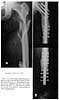

Preop

53 wks

In the 80's, I spent some time in the UK. They had no interlocking nails then andI found a Huckstep nailing kit in the OR closet. (Huckstep-RL Clin-Orthop. 1987Nov(224): 12-25)

Fx

Nail

It has transverse locking screw holes every 2 cm and oblique screw holes at thetop for neck fixation and so it is like a big intramedullary plate. The externaltargeting jig for the screw holes was very rigid and I was able to interlock in aclosed manner. The only problem is that it was a straight, large diameter (12.5mm) device which could comminute a proximal femur (which has already been done inthis case). The other problem was that it was uncannulated so getting it acrossthe various fractures closed without a guide wire can be tricky.

At any rate, if a device like this is available to you, it may be worthconsidering. After a provisional cerclage/reduction of the proximal femoralshaft, you could get good fixation on at least the proximal medial cortex withmultiple locking screws. You could get perhaps 2 screws into the headneck-fragment through the nail and maybe one or two lag screws or Knowles pinsaround the nail.